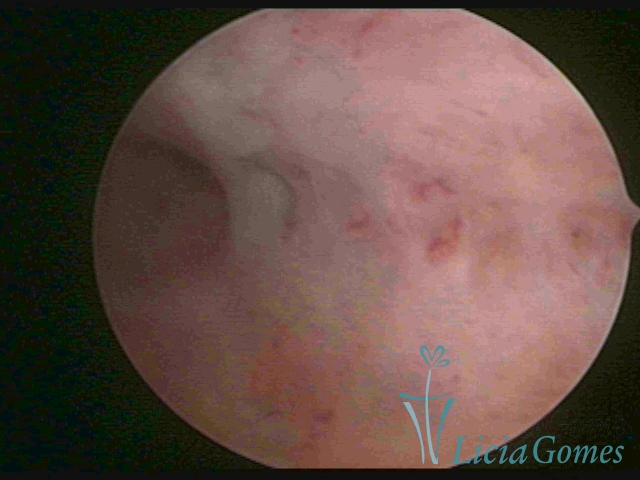

ENDOMETRITE CRÔNICA

Já na Endometrite crônica avançada visualiza-se um endométrio delgado, com áreas desnudas, às vezes, ulcerada, com uma coloração cinza esverdeada com micro varizes, de coloração mais acastanhada, mais acentuada nas regiões cornuais (distrofia vascular).